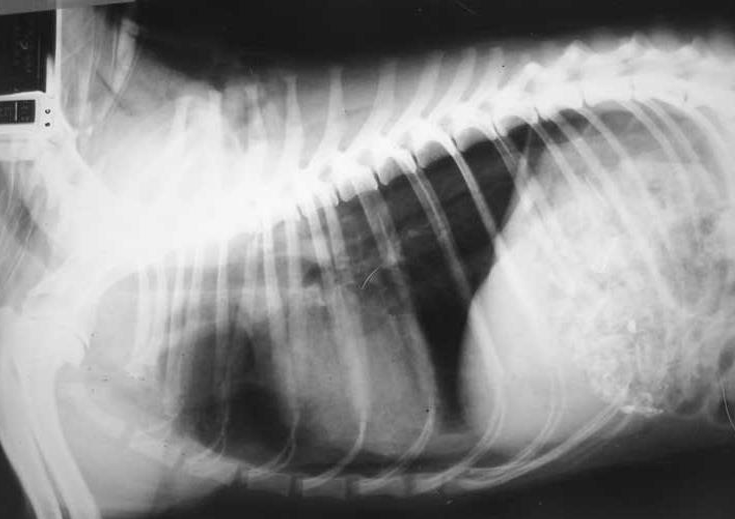

| Case |

| 1-year-old, Mixed breed dog, Death caused by respiratory distress postoperatively |

![]() ![]() |

| - ๋จ๋์ข

์ฆํ๊ตฐ, ํธํก๊ณค๋์ผ๋ก ์์ - contrast ํ์ค (ํ๊ฐ์ด ๋๋ฌด) โ ๊ธฐํ - ET tube ์ฝ๊ด์ผ๋ก ์ธํด trachea๊ฐ ์ฐข์ด์ง โ ์ข ๊ฒฉ๋์ด ๊ณต๊ธฐ๋ก ๊ฝ ์ฐธ. |